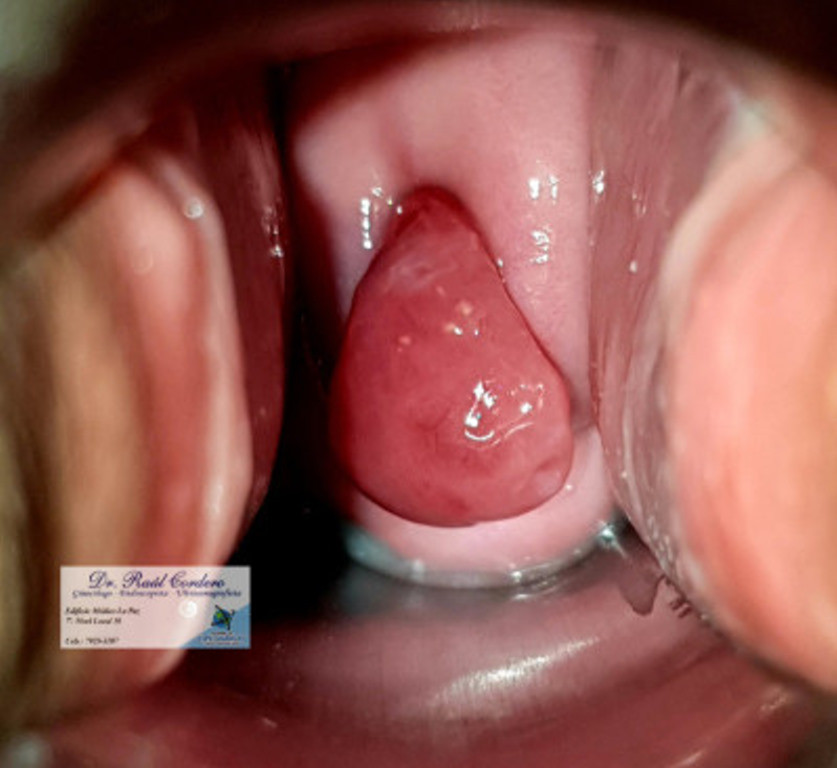

Condilomas Acuminados Vulvares